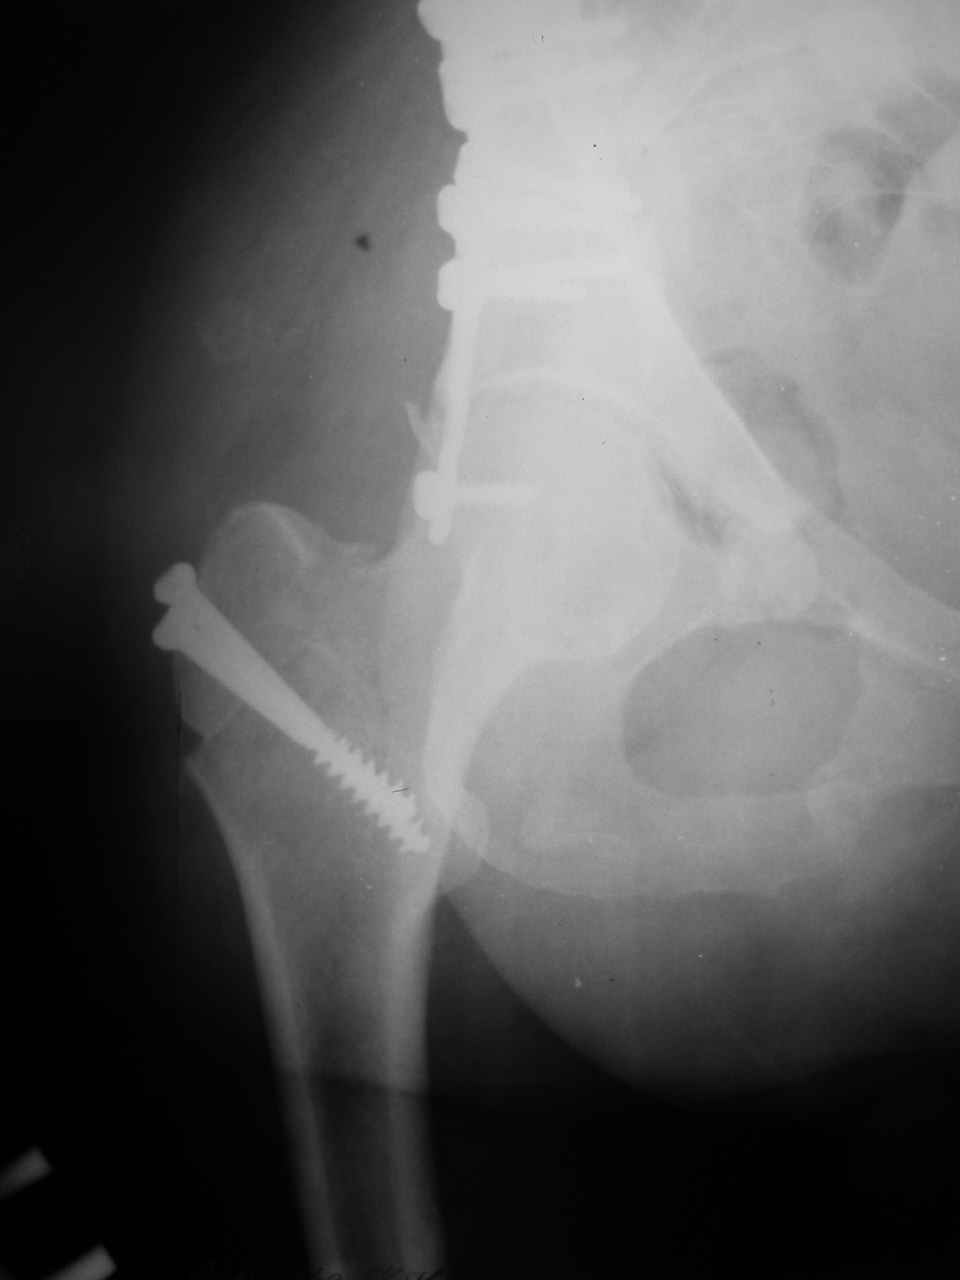

Сложностью, ассоциативностью характера перелома, я бы с радостью воспользовался мининвазивной перкутанной фиксацией винтами, но боюсь, что результат был бы ещё хуже, техникой непрямой репозиции перелома не владею, поэтому пытаясь получить анатомичную впадину приходится широко открывать, по крайней мере пока, а дальше буду пытаться уменьшать пространство...

> передним доступом на двухколонный перелом?

Илеофеморальный доступ не совсем передний и сравнительно с илеоингвинальным, и Кохера-Лангенбека открывает весь наружный таз кроме самых передних отделов лонных костей, фиксацию которых я не ставил в задачу. Обширность диссекции, большая длительность операции и более высокий риск гетерооссификации - отрицательные моменты в обмен на возможность легче ориентироваться.

Комбинированные доступы - хорошая альтернатива, меньший процент осложнений, но я заметил , что без сбора *мозаики* безымянной кости сложно отрепонировать переднюю колонну, а с нерепонированной передней колонной невозможно анатомично собрать заднюю колонну и соотв. фрагменты стенки - так.что все равно открывать придется широко. Поэтому выбирая комбинированный

подход, передний доступ должен был бы быть продлен до задней трети крыла безымянной кости, а задний - практически до того же уровня, оставляя 6-7 см мостик. При этом вместо одного послеоп. рубца у больного остаются два сравнительно длинных.